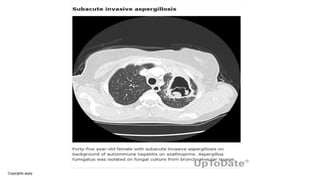

Subacute invasive aspergillosis (SAIA)

• Subacute invasive aspergillosis (SAIA) was previously termed

chronic necrotising or semi-invasive pulmonary aspergillosis. SAIA

occurs in mildly immunocompromised or very debilitated patients

and has similar clinical and radiological features to CCPA but is more

rapid in progression.

• Radiographic findings may include infiltrates, nodules, and

consolidation with or without cavitation; the most common

finding is a single area of consolidation. Unlike other forms of

CPA, pre-existing structural lung disease or cavitation is not

necessary for the development of SAIA.

Subacute invasive aspergillosis in a patient with hepatocellular carcinoma being treated with the sorafenib (a

multityrosine and Raf kinase inhibitor with some immunosuppressive features against T-cells). a) The chest

radiograph shows a large irregular righ...

David W. Denning et al. Eur Respir J 2016;47:45-68

©2016 by European Respiratory Society

Copyrights apply